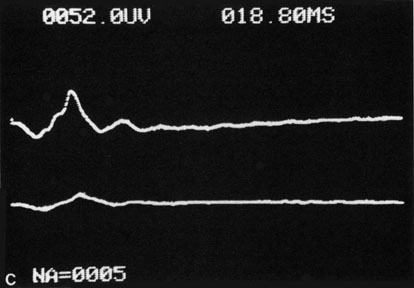

The electroretinogram (ERG) is usually abnormal in central retinal artery obstruction. The b-wave is reduced, indicating a marked abnormality in the circulation of the inner retina.17,18 The a-wave, indicating normal photoreceptor function, is preserved or accentuated. There does not appear to be a good correlation, however, between the extent of b-wave abnormality and the degree of retinal function,3 although Yotsukura and Adachi-Usami420 reported that the b-wave amplitude increased with visual improvement. The photopic negative response (PhNR) shows severe depression in this condition reflecting the significant loss of the ganglion cells and their axons.377 The electrooculogram may be either normal or abnormal. Visual field defects are usually profound but either occasionally a small portion of the temporal peripheral visual field remains or the patient has a large central scotoma.3 The onset of obstruction occurs most often between the hours of midnight and 6 AM, with the second most common period being between 6 AM and noon.2